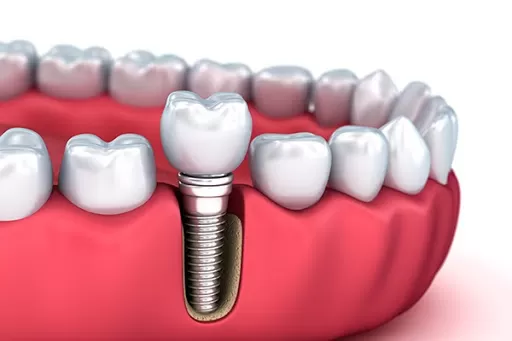

Implant là một vít nhỏ có kích cỡ bằng một chân răng thật được làm bằng Titanium và đặt trong xương hàm thông qua phẫu thuật. Nếu bạn bị mất răng (một hoặc nhiều cái), muốn làm răng giả nhưng vẫn muốn bảo tồn các răng khỏe còn lại, hồi phục khả năng ăn nhai tương đương răng thật nhưng vẫn đảm bảo hoàn toàn tính thẩm mỹ, bác sĩ sẽ tư vấn bạn trồng Implant.

Quy trình trồng Implant gồm có 2 bước. Đầu tiên, các bác sĩ sẽ thăm khám, sau đó cấy ghép 1 trụ Titanium vào xương hàm để thay thế cho chân răng đã mất. Trong khoảng thời gian từ 4 – 6 tháng sau, khi trụ Implant đã được tích hợp vững chắc vào xương hàm, bạn sẽ được gắn phục răng sứ trên trụ đã ghép.

Như vậy Implant được hiểu như “chân răng nhân tạo” nâng đỡ cho răng sứ bên trên. Phục hình trên Implant sẽ được làm đúng theo hình dạng và kích thước của răng thật, đem lại cảm giác dễ chịu và khôi phục được đến 90% khả năng ăn, nhai như răng thật.

Răng Implant gồm có một trụ implant nhân tạo có thiết kế dạng xoắn ốc được làm từ vật liệu titanium. Trụ này được gắn chặt vào xương hàm bằng kỹ thuật cấy ghép Implant hiện đại, gắn kết với xương hàm thành một thể thống nhất vững chắc. Chính vì thế, răng Implant những ưu điểm nổi bật mà các kỹ thuật khác không có được như: